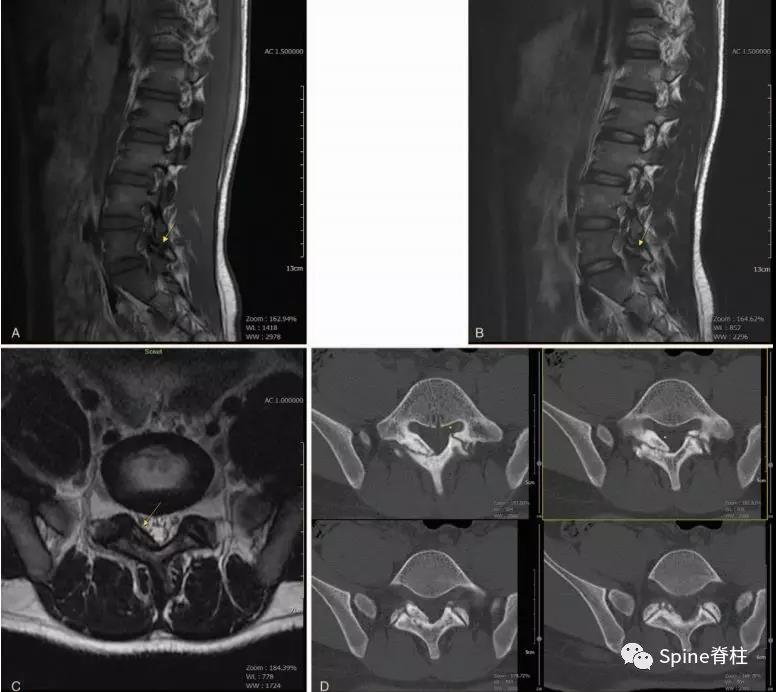

图:15岁腰痛男孩,左侧腰5椎弓根裂A:T1左侧腰5椎弓根低信号(箭头);B:T2左侧腰5椎弓根高信号(箭头);C:T2轴位左侧腰5椎弓根骨折线明显,伴高信号区(箭头)